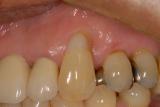

根面被覆(ルートカバレッジ) | ||

| 歯ぐきが薄い所は歯ぐきが下がりやすです。詰め物をしても詰め物の刺激でまた歯ぐきが下がってしまいます。再生療法により、露出根面をカバーし厚い歯ぐきを獲得しました。審美的にも改善され、歯ぐきも下がりにくくなりました。現在の歯科医療は進んでいます。 | ![]() |